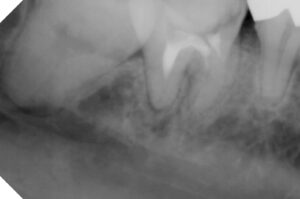

2017年8月 再来時に左下第二大臼歯のレントゲン

を撮り処置途中歯の被せ物の相談をするもそのままに

根の処置が上手くいかないことを説明し、保険で

土台と冠を被せることで納得していただきました。

レントゲンでは神経の詰め物の状態の違い→